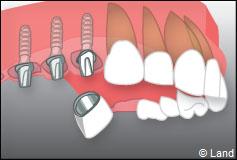

Exemple de 3 dents manquantes remplacées par 3 couronnes sur implants.

Pose des piliers prothétiques et des 3 couronnes scellées.